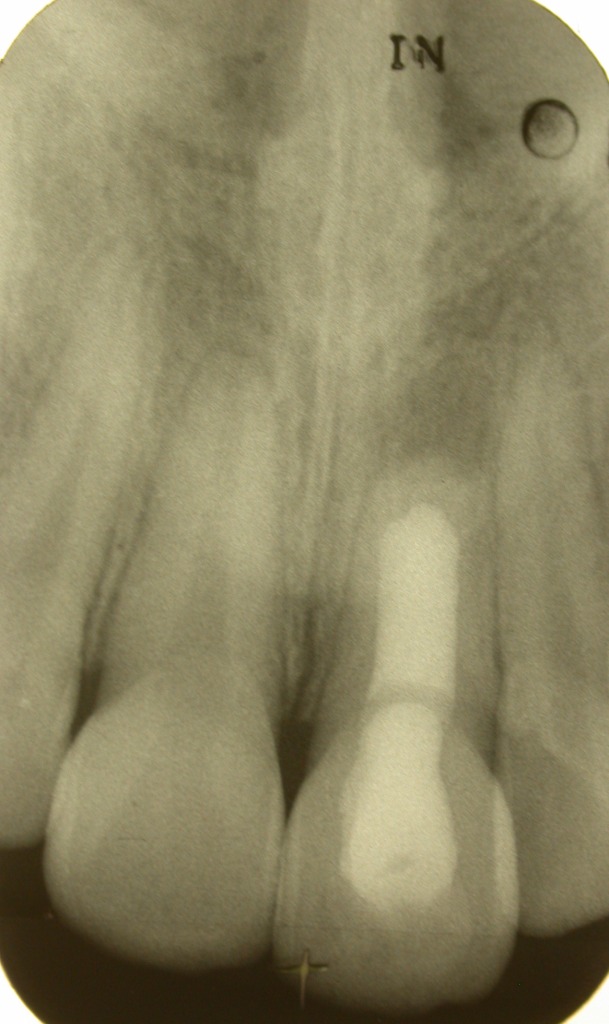

Tot voor kort werd de open apex vrijwel standaard afgesloten middels een zogenaamde “apexificatie” met behulp van Ca(OH)2. Als er dan een dentinebrug was gevormd werd daar de kanaalvulling tegenaan geplaatst. Vaak was dit een langdurige en tijdrovende behandeling waarvan de goede afloop lang niet altijd zeker was.

De nieuwste methode met de beste prognose is het afsluiten met

MTA (Pro Root)

.

Dit gebeurt als volgt:

In de eerste zitting wordt op de gebruikelijke manier geprepareerd en gespoeld. Vervolgens wordt er gedurende minstens een week

CA(OH)2 in het wortelkanaal aangebracht.